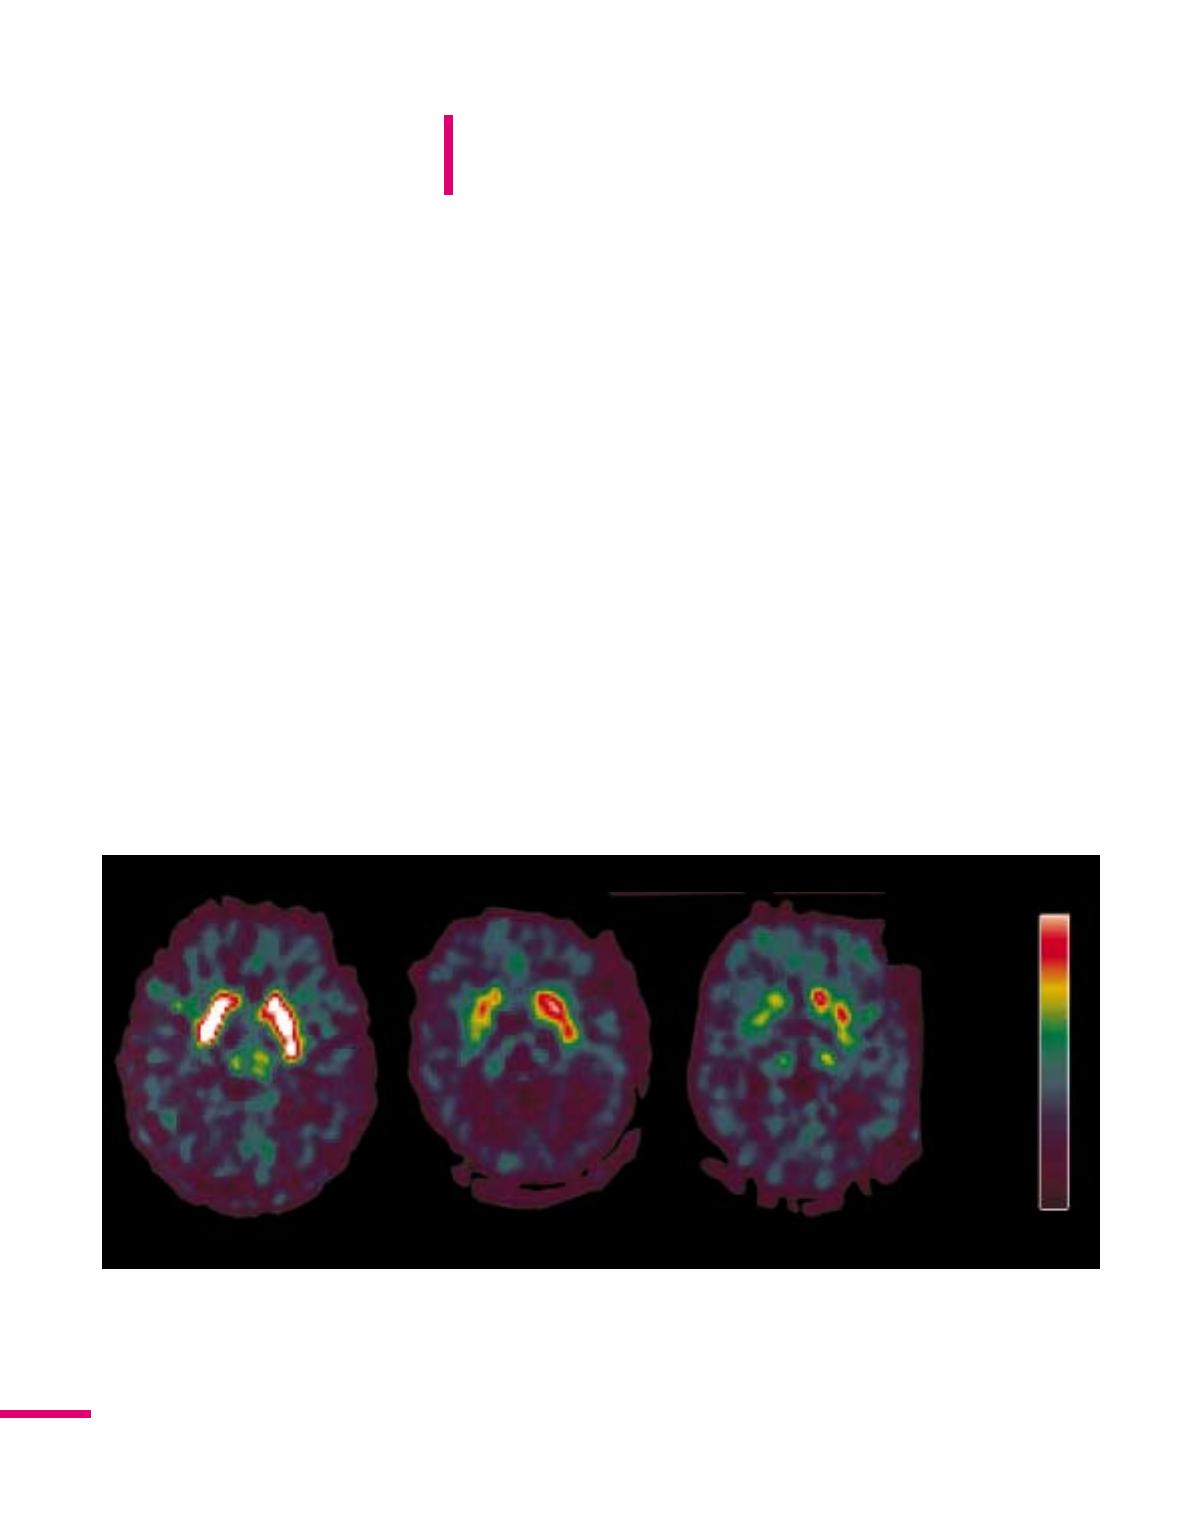

Témoin Parkinsonien de novo Parkinsonien sévère

Figure 1. Captage striatal de la 18F-Dopa chez un sujet normal, un parkinsonien débutant et un parkinsonien sévère.

Le captage du traceur est montré sur une coupe axiale (transverse) au niveau du striatum. La gauche des images cor-

respond à la droite du cerveau. On constate chez le parkinsonien débutant (stade I de Hoehn et Yahr, jamais traité)

une diminution de la fixation du traceur prédominant dans les régions postérieures du striatum (putamen postérieur)

et asymétrique (plus marquée à droite). Cette asymétrie correspond à l’asymétrie des signes de la maladie. Chez un

patient sévère, au stade IV de Hoehn et Yahr, la diminution de captage du traceur est plus marquée et s’étend plus

vers l’avant du striatum (putamen antérieur, noyau caudé). Elle reste asymétrique avec un captage effondré à droite.